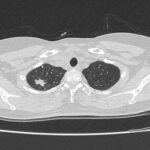

CASE LÂM SÀNG Điều trị bệnh nhân mắc đồng thời hai loại ung thư: Ung thư phổi và ung thư tuyến tiền liệt

CASE LÂM SÀNG Điều trị bệnh nhân mắc đồng thời hai loại ung thư: Ung thư phổi và ung thư...